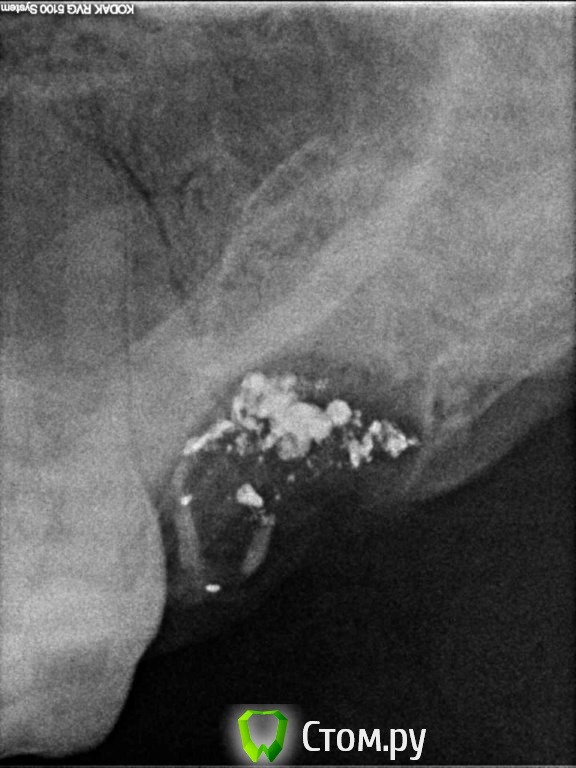

tunica Опубликовано 18 декабря, 2013 Поделиться Опубликовано 18 декабря, 2013 27-й зуб был удален 29 ноября с перфорацией гайморовой пазухи, лунку закрыли альвожелем и марлевой турундой. 6 декабря припухлость со стороны щеки , марлевую повязку убрали, заложили альвожель . 8 декабря, после промывания лунки антисептиком и закладывания альвожеля, был сделан снимок. Врач клиники, где удалялся зуб, сказал что на снимке все в норме.Область над удаленным зубом со стороны щеки продолжает болеть по сей день, периодически опухая. Посетила ЛОР-врача, ЛОР исключил гайморит. Пока пью антибиотики. Уважаемые специалисты,прикладываю снимок. Подскажите, есть ли здесь трещина кости ( просвет рядом с корнем 26 зуба) или это что-то другое и может ли из-за этого так долго болеть щека? Ссылка на комментарий

Bier Опубликовано 18 декабря, 2013 Поделиться Опубликовано 18 декабря, 2013 нет, перелома у вас нет.возможно альвеолит 1 Ссылка на комментарий